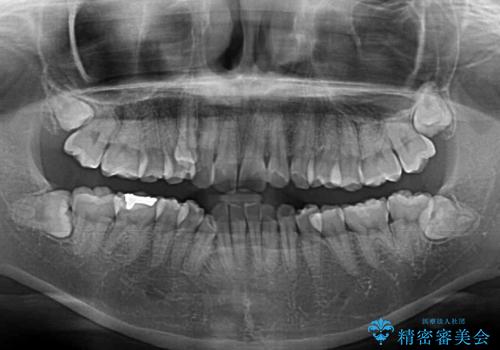

八重歯の抜歯矯正 補助装置とワイヤーを併用したインビザライン矯正治療

- 八重歯と上顎正中のズレを気にして来院された患者様です。

インビザラインによる矯正治療を希望されたため、八重歯改善のための抜歯矯正部分や上顎正中の大幅に位置移動は、補助装置やワイヤー矯正を併用し、その後はインビザラインにて行うこととしました。

骨格的に下顎が左側に変位していたため、上下正中を合わせることは困難であることは分かっていましたが、可能な限り合わせることができました。

骨格的なズレがあると仕上げの段階で奥歯の咬み合わせが不安定となるため、予定よりやや長期間となりました。